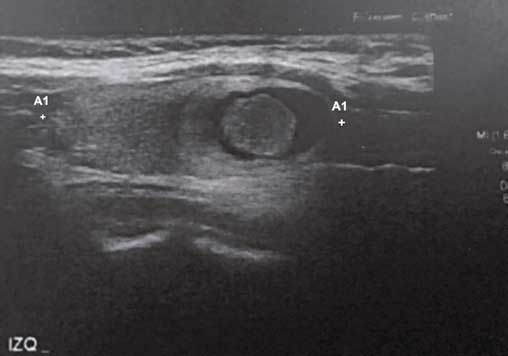

Paciente género femenino, 36 años, enfermera. Consulta el año 2018 por aumento volumen cervical indoloro, lateralizado a izquierda, de un mes de evolución. Sin antecedentes personales mórbidos previos, sin exposición a radioterapia externa previa. Hermana con hipotiroidismo primario. Sin uso de medicamentos. Al examen físico destacaba nódulo tiroideo palpable, móvil, no doloroso, no adherido a planos profundos, sin adenopatías palpables. Resto del examen físico normal. Se realizó ecografía tiroidea que evidenció “un nódulo tiroideo izquierdo con transformación quística excéntrica la cual posee otra imagen nodular en su interior parcialmente vascularizada de 20x12x19 mm” (Figura 1). Bioquímica con TSH 0,33 (VN 0,3-5,0), T4 libre 0,92 (VN 0,7-2,0), anticuerpo AntiTPO < 60, anticuerpo antitiroglobulina < 30. Se realizó biopsia PAF con resultado “Hallazgos corresponden a atipías de significado indeterminado (Bethesda III)”. Se discutió alternativas a seguir con paciente, y debido a una alta aprehensión personal quiso someterse de una tiroidectomía total. Un primer informe de la biopsia definitiva mostró “lesión quística de pared fibrosa de 2x1,7 cm y con nódulo central de 1,3 cm correspondiente a Tumor bien diferenciado de potencial maligno incierto”. Una segunda revisión de la biopsia la reclasificó en “Neoplasia folicular tiroidea no invasiva con características nucleares de tipo papilar (NIFTP)” (Figura 2). La paciente evoluciona en forma favorable posterior a cirugía, con sustitución de levotiroxina, y no recibió yodo radioactivo.

Figura 1: Ecografía tiroidea paciente. Nódulo tiroideo izquierdo con transformación

quística excéntrica la cual posee otra imagen nodular, de 20x12x19 mm.